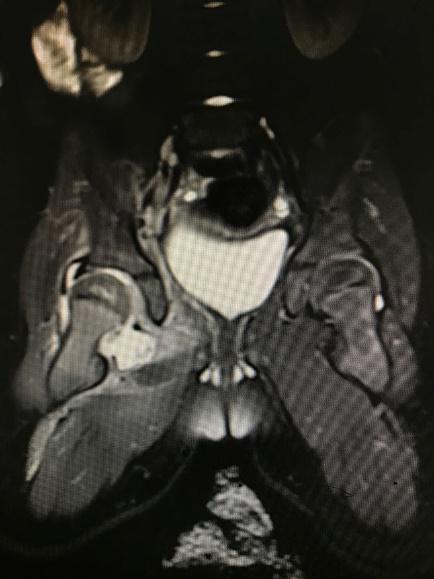

1 资料与方法 1.1 一般资料本研究为回顾性研究,获得医院医学伦理委员会审批(审编号:2020-IRB-035),通过检索本院的电子病例系统,搜索2016年1月1日至2018年12月31日期间出院诊断为“化脓性髋关节炎”的所有病例信息。纳入标准:(1)患儿临床症状、体征、影像学检查、关节液液培养、关节腔液白细胞计数(计数≥50 000 / mm3)、手术或病理证实的化脓性髋关节炎,见图 1~4;(2)关节腔穿刺或手术可见脓性标本。排除标准:(1)年龄>3岁;(2)穿刺或手术未能取得足够标本送检细菌培养者。

| 图 1 B超示关节腔内积液 |